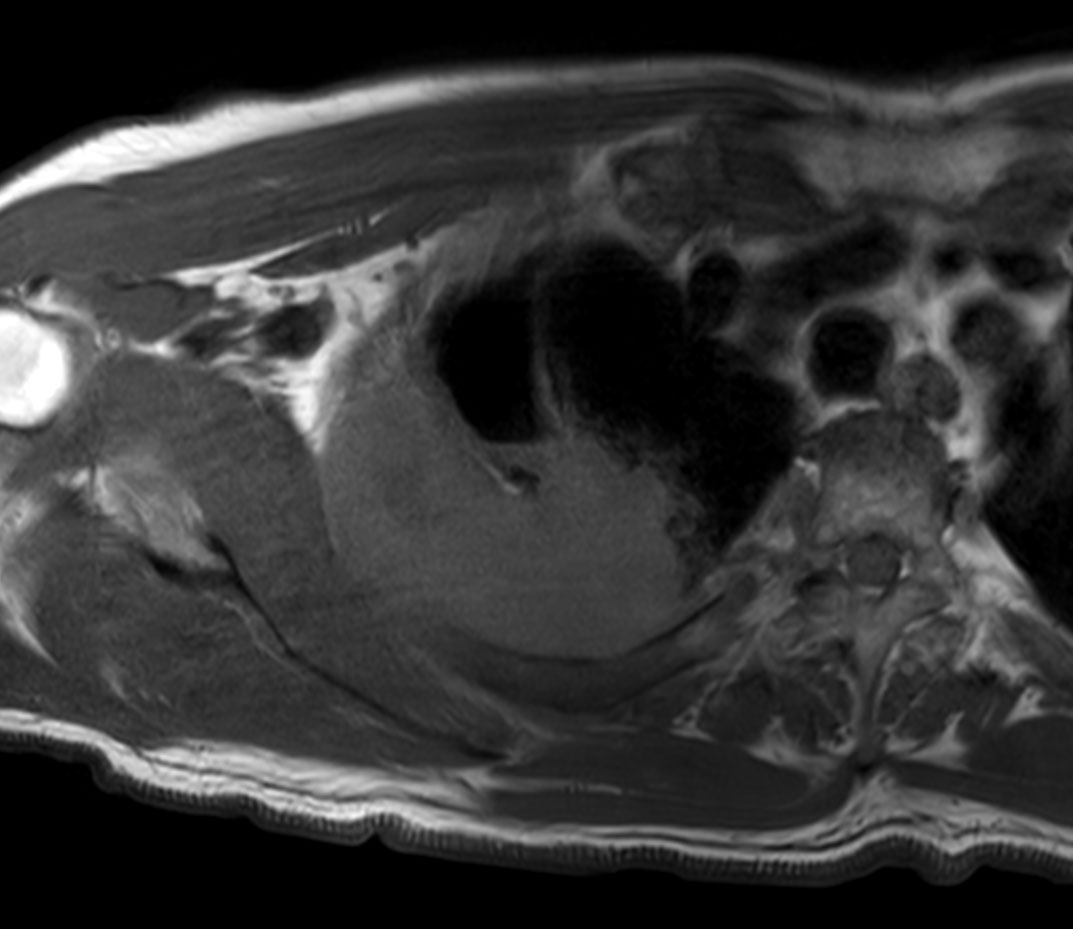

Axial T1w TSE